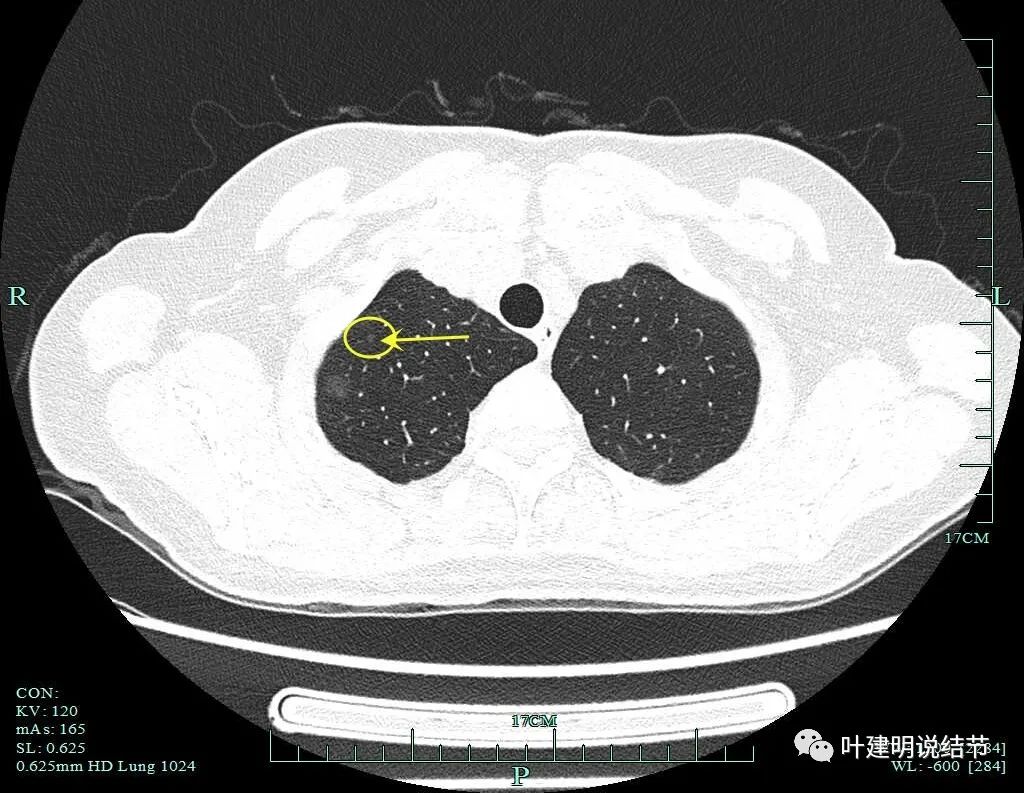

病灶9:右中叶实性结节,密度过高,小而实的结节以良性可能性大。

我们手术前做了靶扫描的重建,但当时请影像做的是病灶2、病灶6和病灶8。我的纠结在于中叶这个实性病灶是什么?如果它是炎性的或肺内淋巴结,密度是不是要更高一点?两肺这么多结节都考虑肿瘤范畴,只有这处是炎性或良性的,好像说不大通。我们以前也一直强调:如果多发结节,有的良恶性难定,有的较为明确是恶性,那么难定的也很可能同样的恶性的;有的较为明确是炎性的,那么难定的这处也可能是炎性的,因为致病的因素是一样的。有了这个念头之后,再回头去看中叶的结节,怎么总觉得虽像实性,但不够密实。所以我打电话请影像科同事重新为她中叶这颗也靶重建一下看看细节信息。

病灶9的重建发现不是实性结节,而混合磨玻璃密度。绿色箭头示边上有磨玻璃成分,而且紫色箭头示边缘是毛糙的,红色箭头示整体轮廓是清的。

上图也显示病灶边缘毛糙,不光滑,与胶原结节、淋巴结等良性结节是不符合的。

影像再判断:

右肺中叶病灶9考虑是浸润性腺癌,比其他病灶风险都高,它应该是主病灶了。但鉴于两肺多发病灶基本上都考虑肿瘤范畴的,即使此灶考虑浸润性,但毕竟还小,也有磨玻璃成分,存在转移的概率极小,仍应该可以考虑妥协性的楔形切除。